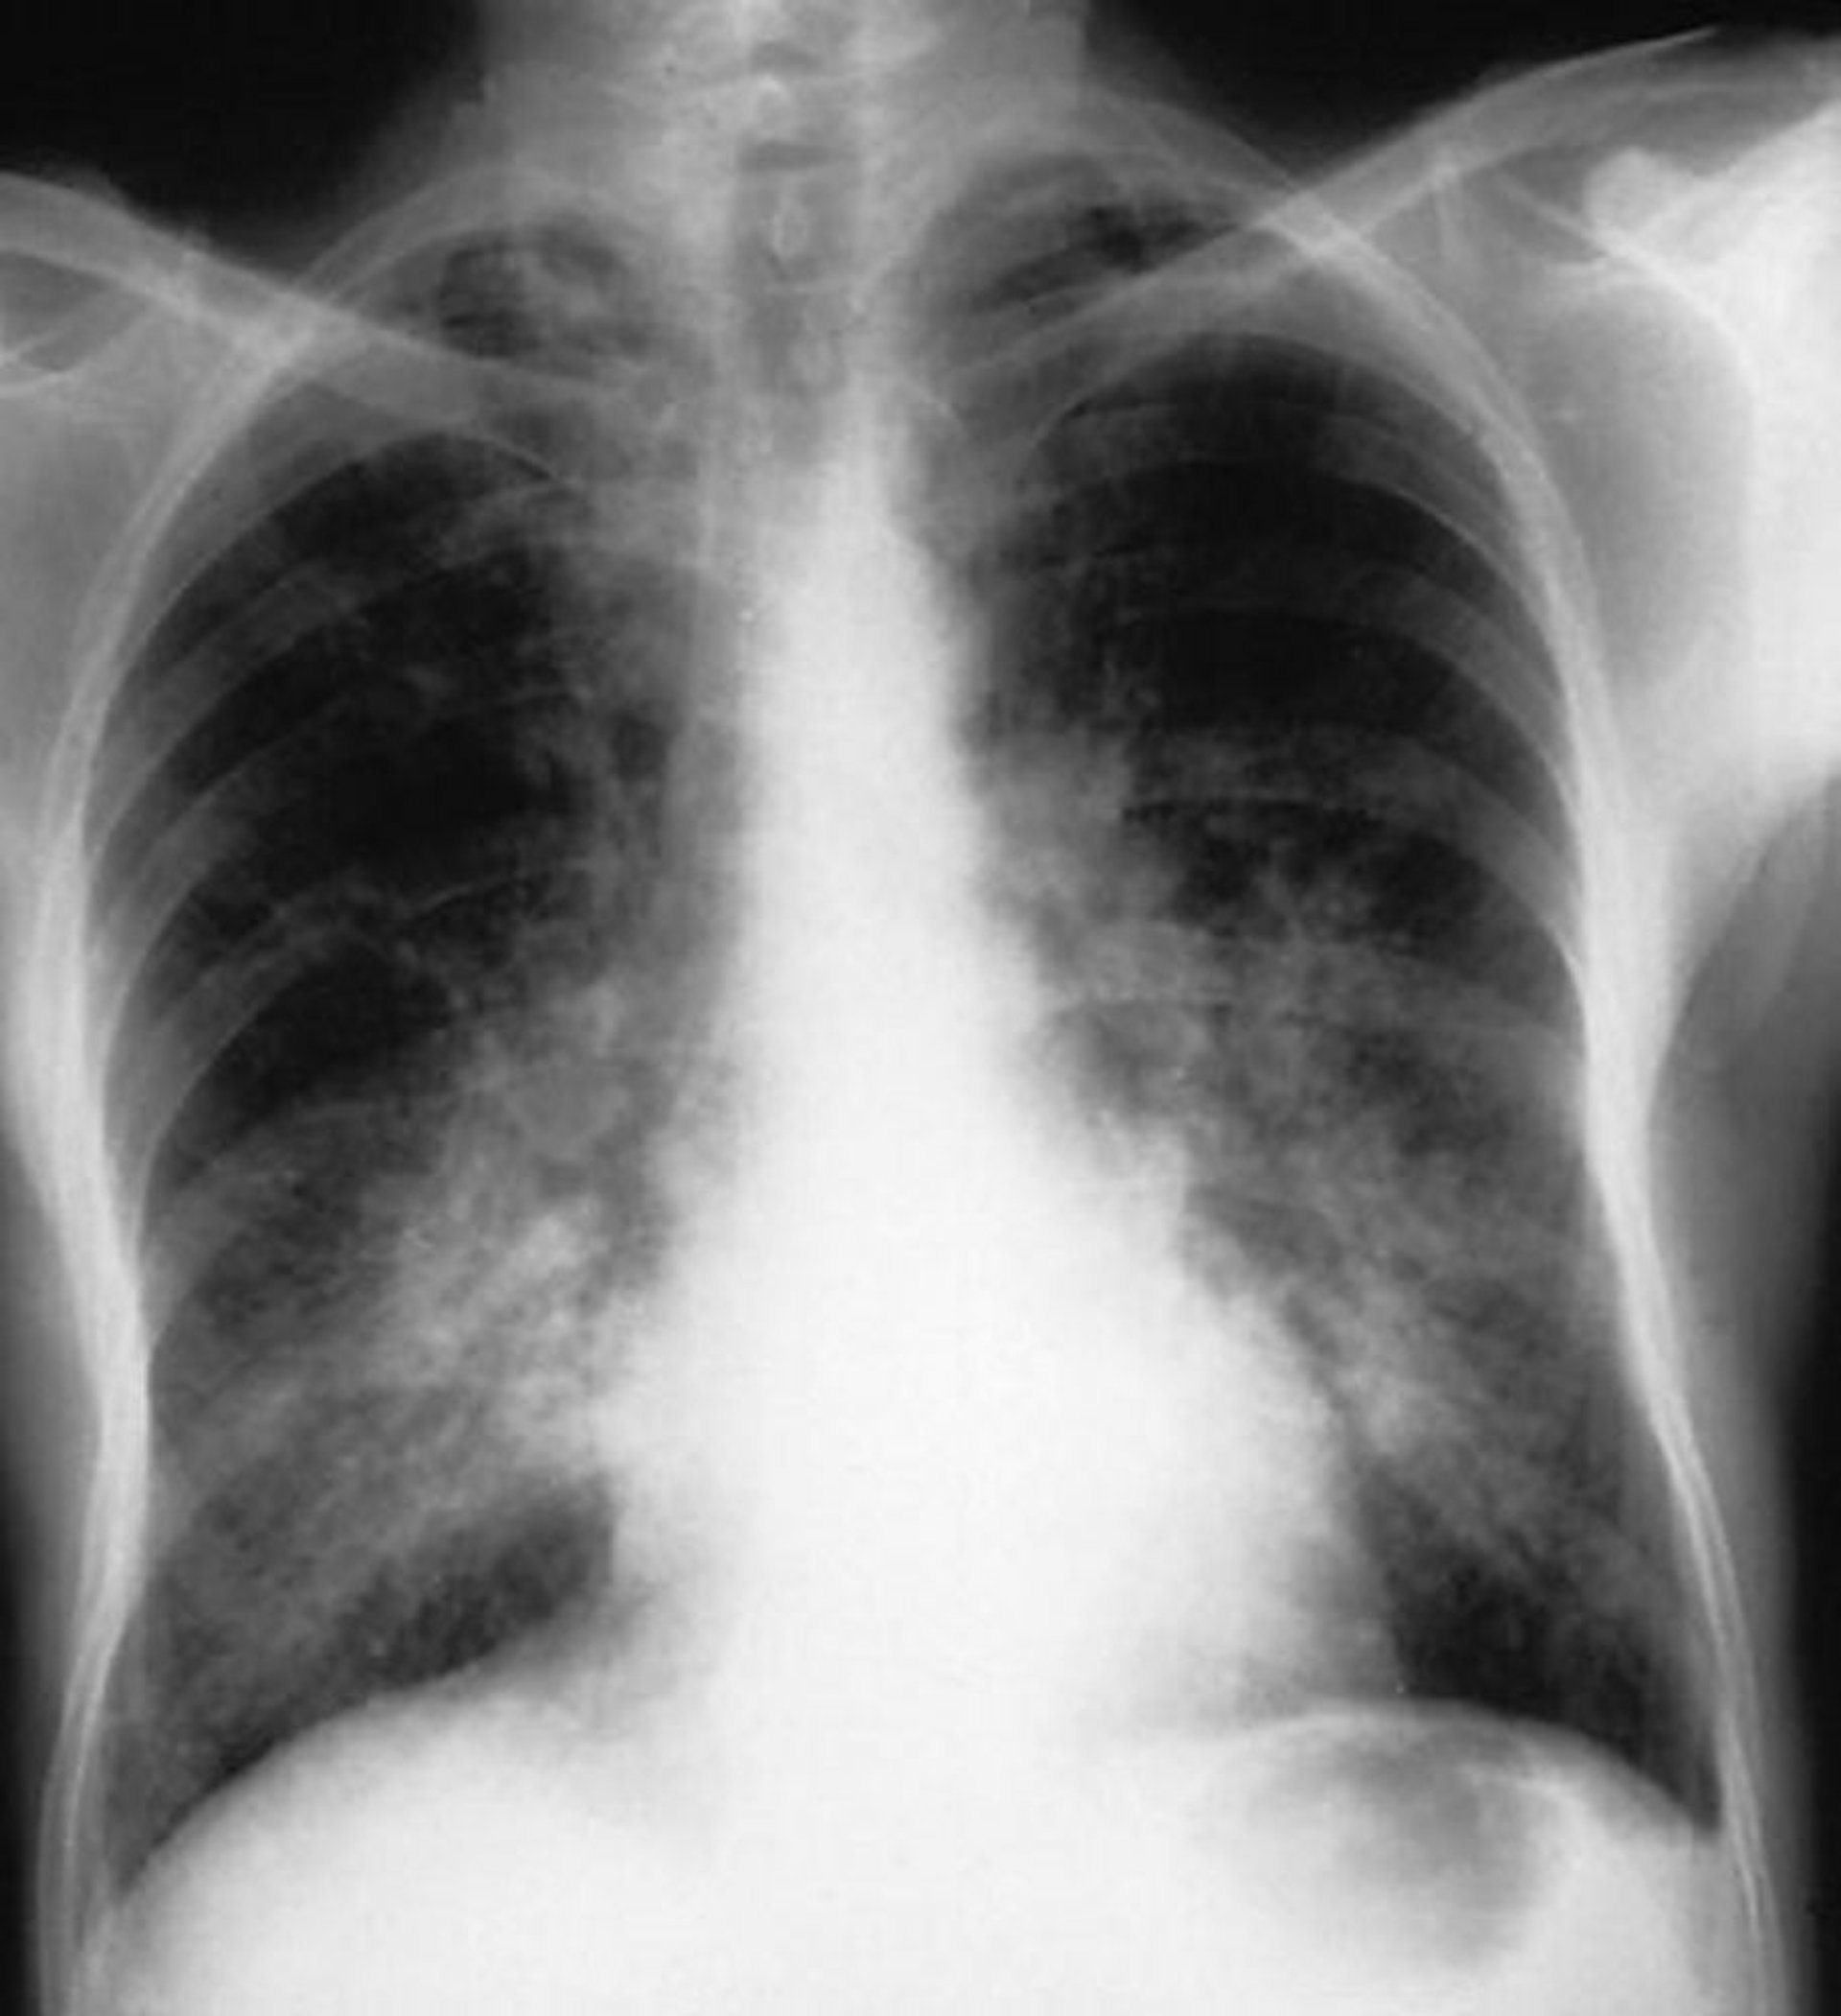

Альвеолярное кровотечение

Эта рентгенография грудной клетки показывает двустороннее затемнение в области альвеол у пациента с альвеолярным кровотечением.

By permission of the publisher. From Cohen A, Glassock R. In Atlas of Diseases of the Kidney: Glomerulonephritis and Vasculitis. Edited by R Schrier (series editor), RJ Glassock, and AH Cohen. Philadelphia, Current Medicine, 1999.